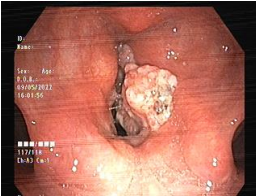

Figures 1,2,3,4

Figure 3